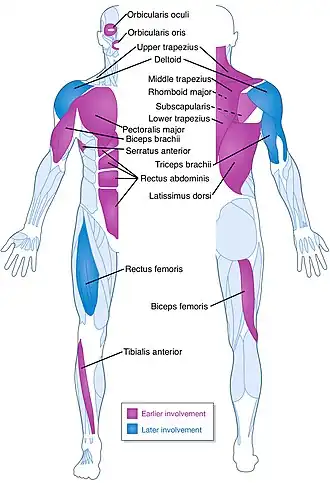

| A diagram showing the muscles commonly affected by FSHD | |

Facioscapulohumeral muscular dystrophy (FSHD) is a type of muscular dystrophy, a group of heritable diseases that cause degeneration of muscle and progressive weakness. Per the name, FSHD tends to sequentially weaken the muscles of the face, those that position the scapula, and those overlying the humerus bone of the upper arm.[2][3] These areas can be spared. Muscles of other areas usually are affected, especially those of the chest, abdomen, spine, and shin. Most skeletal muscle can be affected in advanced disease. Abnormally positioned, termed 'winged', scapulas are common, as is the inability to lift the foot, known as foot drop. The two sides of the body are often affected unequally. Weakness typically manifests at ages 15–30 years.[4] FSHD can also cause hearing loss and blood vessel abnormalities at the back of the eye.

Classically, weakness develops in the face, then the shoulder girdle, then the upper arm.[10] These muscles can be spared, and other muscles usually are affected. The order of muscle involvement can cause the appearance of weakness, "descending" from the face to the legs.[10] The distribution and degree of muscle weakness are extremely variable, even between identical twins.[20][21] Musculoskeletal pain is very common, most often described in the neck, shoulders, lower back, and the back of the knee.[22][4] Fatigue is also common.[4] Muscle weakness usually becomes noticeable on one side of the body before the other, a disease hallmark.[14] The right shoulder and arm muscles are more often affected than the left upper extremity muscles, independent of handedness.[23]: 139 [24][25][26] Otherwise, neither side of the body is at more risk. Classically, symptoms appear in those 15–30 years old, although adult onset can also occur.[4] Infantile-onset (also called early-onset), defined as onset before age 10, occurs in 10% of affected individuals.[10] FSHD1 with a substantial D4Z4 deletion (EcoRI 10-11 kb) is more strongly associated with infantile-onset and severe weakness.[27] Absence or near absence of symptoms is not uncommon, approaching up to 30% of mutation-carrying individuals in select FSHD1 families.[10] On average, FSHD2 presents 10 years later than FSHD1.[28] Otherwise, FSHD1 and FSHD2 are indistinguishable on the basis of weakness.[27] Disease progression is slow, and long static phases, in which no progression is apparent, are not uncommon.[29] Less commonly, individual muscles rapidly deteriorate over several months.[2] The symptom burden of FSHD is typically more severe than it is perceived to be by those without the disease.[30][31][32][33]

Shoulder, chest, and arm

After the facial weakness, weakness usually develops in the muscles of the chest and those that span from the scapula to the thorax. Symptoms involving the shoulder, such as difficulty working with the arms overhead, are the initial complaint in 80% of cases.[24][14] Predominantly, the serratus anterior and middle and lower trapezii muscles are affected;[4] the upper trapezius is often spared.[14] Trapezius weakness causes the scapulas to become downwardly rotated and protracted, resulting in winged scapulas, horizontal clavicles, and sloping shoulders; arm abduction is impaired. Serratus anterior weakness impairs arm flexion, and worsening of winging can be demonstrated when pushing against a wall. Muscles spanning from the scapula to the arm are generally spared, which include the deltoid and the rotator cuff muscles.[37][38] The deltoid can be affected later on, especially the upper portion.[4]

Severe muscle wasting can make bones and spared shoulder muscles very visible, a characteristic example being the "poly-hill" sign elicited by arm elevation.[4] The first "hill" or bump is the upper corner of scapula appearing to "herniate" up and over the rib cage. The second hill is the AC joint, seen between a wasted upper trapezius and wasted upper deltoid. The third hill is the lower deltoid, distinguishable from the wasted upper deltoid and wasted humeral muscles.[4] Shoulder weakness and pain can, in turn, lead to shoulder instability, such as recurrent dislocation, subluxation, or downward translation of the humeral head.[39]

Also affected is the chest, particularly the parts of the pectoralis major muscle that connect to the sternum and ribs. The part that connects to the clavicle is less often affected. This muscle-wasting pattern can contribute to a prominent horizontal anterior axillary fold.[40][4] Beyond this point, the disease does not progress further in 30% of familial cases.[24][14] After upper torso weakness, weakness can "descend" to the upper arms (biceps muscle and, particularly, the triceps muscle).[24] The forearms are usually spared, resulting in an appearance some compare to the fictional character Popeye.[4] When the forearms are affected in advanced disease, the wrist extensors are more often affected.[24]

Lower body and trunk

After the upper body, weakness can next appear in either the pelvis or it "skips" the pelvis and involves the tibialis anterior (shin muscle), causing foot drop. One author considers the pelvic and thigh muscles the last group affected.[24] Pelvic weakness can manifest as a Trendelenburg's sign.[4] Weakness of the back of the thigh (hamstrings) is more common than weakness of the front of the thigh (quadriceps).[4] In more severe cases, especially infantile FSHD, there can be anterior pelvic tilt, with associated hyperextension of the knees.[41]

Weakness can also occur in the abdominal muscles and paraspinal muscles, which can manifest as a protuberant abdomen and lumbar hyperlordosis.[2][4] Abdominal weakness can cause inability to do a sit-up or the inability to turn from one side to the other while lying on one's back.[4] Of the rectus abdominis muscle, the lower portion is preferentially affected, manifesting as a positive Beevor's sign.[4][2] In advanced cases, neck extensor weakness can cause the head to lean towards the chest, termed head drop.[24]